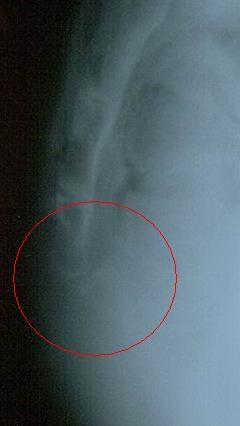

Вывих копчика!!!!!!

Название изображения: Вывих копчика!!!!!!